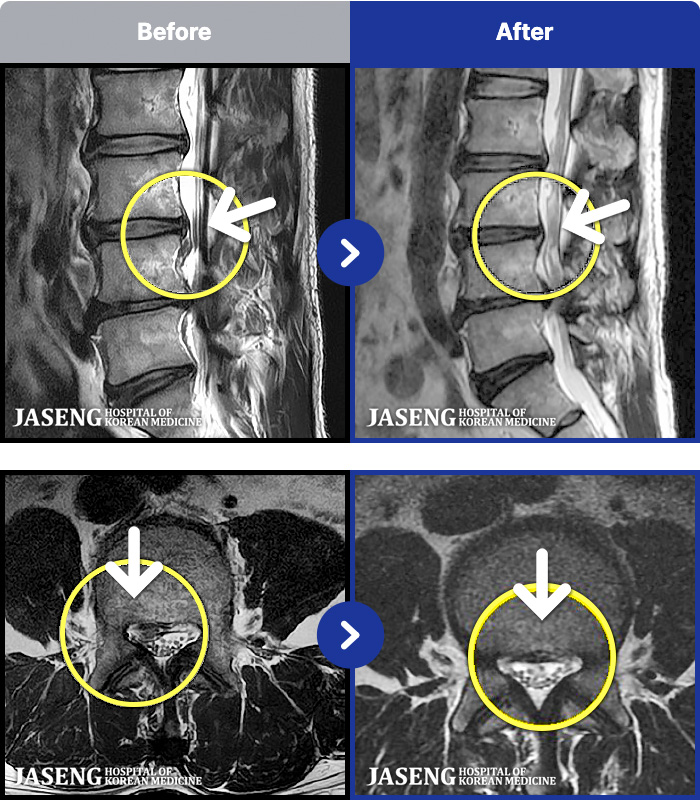

MRI ġ

54 MRI ũ ʸ Ȯϼ.

[Կñ:21.12.17~22.07.04]

[_㸮ũ] 㸮

No.53

ȸ 212

2026.01.09